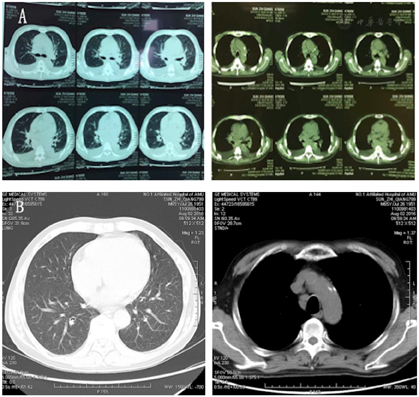

患者,男性,65岁,系"心悸胸闷气喘伴咳嗽咳痰2年,纳差2个月余"入院。患者2年前无明显下出现心悸、胸闷气喘、咳嗽咳痰,伴有面部结节样皮疹(图1),入住安徽医科大学第一附属医院心内科,予以完善相关检查,患者血常规示:白细胞计数3.18×109/L,血红蛋白85 g/L;BNP 1 560 pg/ml;心电图示:心房颤动(心室率快);动态心电图示:频发多源室早、房早;心脏彩超示:全心增大,整体心肌活动受抑,EF:0.37,肺动脉压42 mmHg(1 mmHg=0.133 kPa)。考虑诊断"心律失常,心力衰竭,贫血,肺部感染",经强心、利尿、扩管、抗感染、抗心律失常、纠正贫血等治疗后患者胸闷气喘、咳嗽咳痰好转。在院期间完善肺部CT提示纵膈淋巴结肿大,右下肺门影增大,转移癌,淋巴瘤不能除外(图2A),故完善PET-CT考虑双肺门及纵膈多发淋巴结转移癌,全身多发骨转移(图3A)。后患者前往上海就诊,外院行骨髓活检提示骨髓造血组织增生活跃,未见明显异常细胞。双侧髂骨活检病理提示上皮样肉芽肿性病变,请排除结节病后,首先考虑血行播散性结核可能,病理形态和免疫标记结果不支持转移性癌。考虑患者无发热、盗汗等症状,T-SPOT(-),骨髓抗酸染色阴性,未见干酪样坏死,故排除结核,诊断为"结节病"。予以醋酸泼尼松15 mg qd,环磷酰胺0.4~0.6 g,每月静脉滴注1次,共使用6次,以及沙利度胺,雷公藤等治疗,患者心悸胸闷好转,皮疹减轻,影像学检查提示肿大淋巴结明显缩小或消失(图2B,图3B)。出院后规律服药,醋酸泼尼松逐渐减量为5 mg qd,定期门诊随访。2个月前患者无明显诱因下出现納差,就诊于安徽医科大学第一附属医院风湿免疫科门诊,拟"结节病"收入院。患者病程中有口眼干、眼痛,无光过敏,无口腔溃病,无脱发,无雷诺现象,无发热,无腹痛腹泻,睡眠差,二便正常,近期体质量下降7.5 kg。患者妹妹患有干燥综合征。

患者胸闷气喘及咳嗽、心悸、乏力纳差症状明显好转,皮疹减轻,心力衰竭症状好转,肾功能恢复,血常规及炎症指标较前好转,影像学检查肿大淋巴结明显缩小或消失。

患者胸闷气喘及咳嗽、心悸、乏力纳差症状明显好转,皮疹减轻,肾功能恢复,血常规及炎症指标正常,心衰症状好转,影像学检查肿大淋巴结明显缩小或消失。